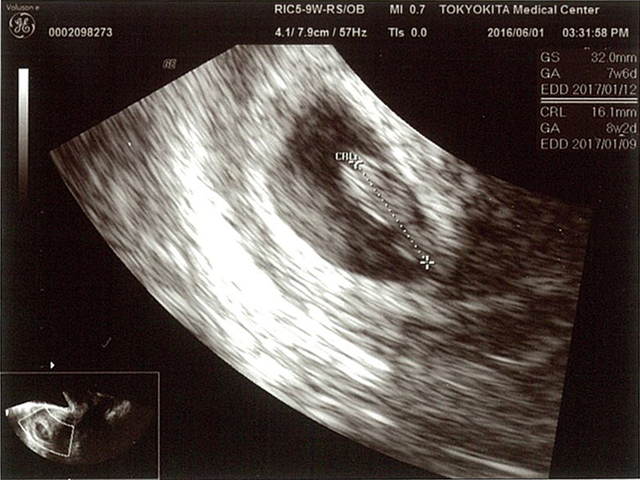

7週1日(7w1d・女の子)|ムーミンぴす さん(35歳)

エコー写真撮影時のエピソード:はじめての移植でできた子でした。

普通の妊娠と違って、早く妊娠がわかるので、健診の度に緊張していました。

エコー写真を見たときパンダみたい!と、すごく可愛いいと思いました。

15日前に見たエコー写真は胎嚢しか見えてなかったので、赤ちゃんが見れたことと、人間ってすごいと感動しました。